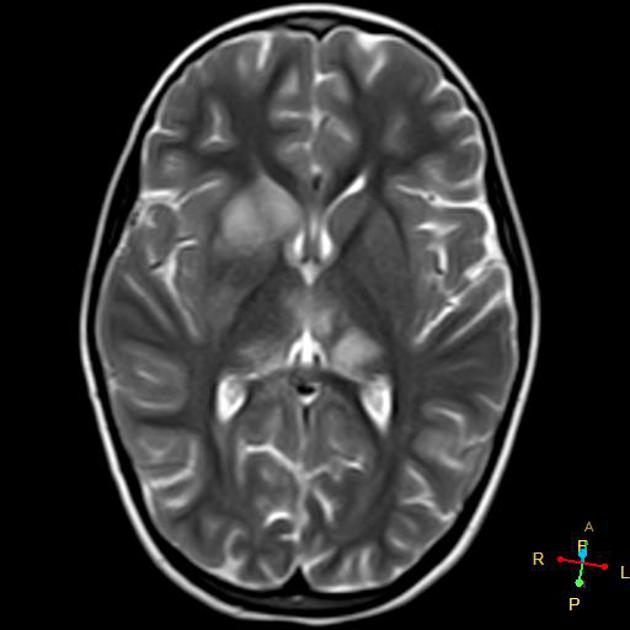

3/ T2-Weighted MRI β Edema & Pathology Detection

π₯οΈ Appearance:

β CSF = Bright

β Edema = Bright

β Gray matter = Bright, White matter = Dark

π Key Uses in Neurosurgery:

β Detects vasogenic & cytotoxic edema (brain tumors, strokes, infections)

β White matter demyelination (MS, PML, leukodystrophies)

β Cystic & necrotic tumor components

π¨ Best for detecting pathological changes!

image: radiopaedia.org